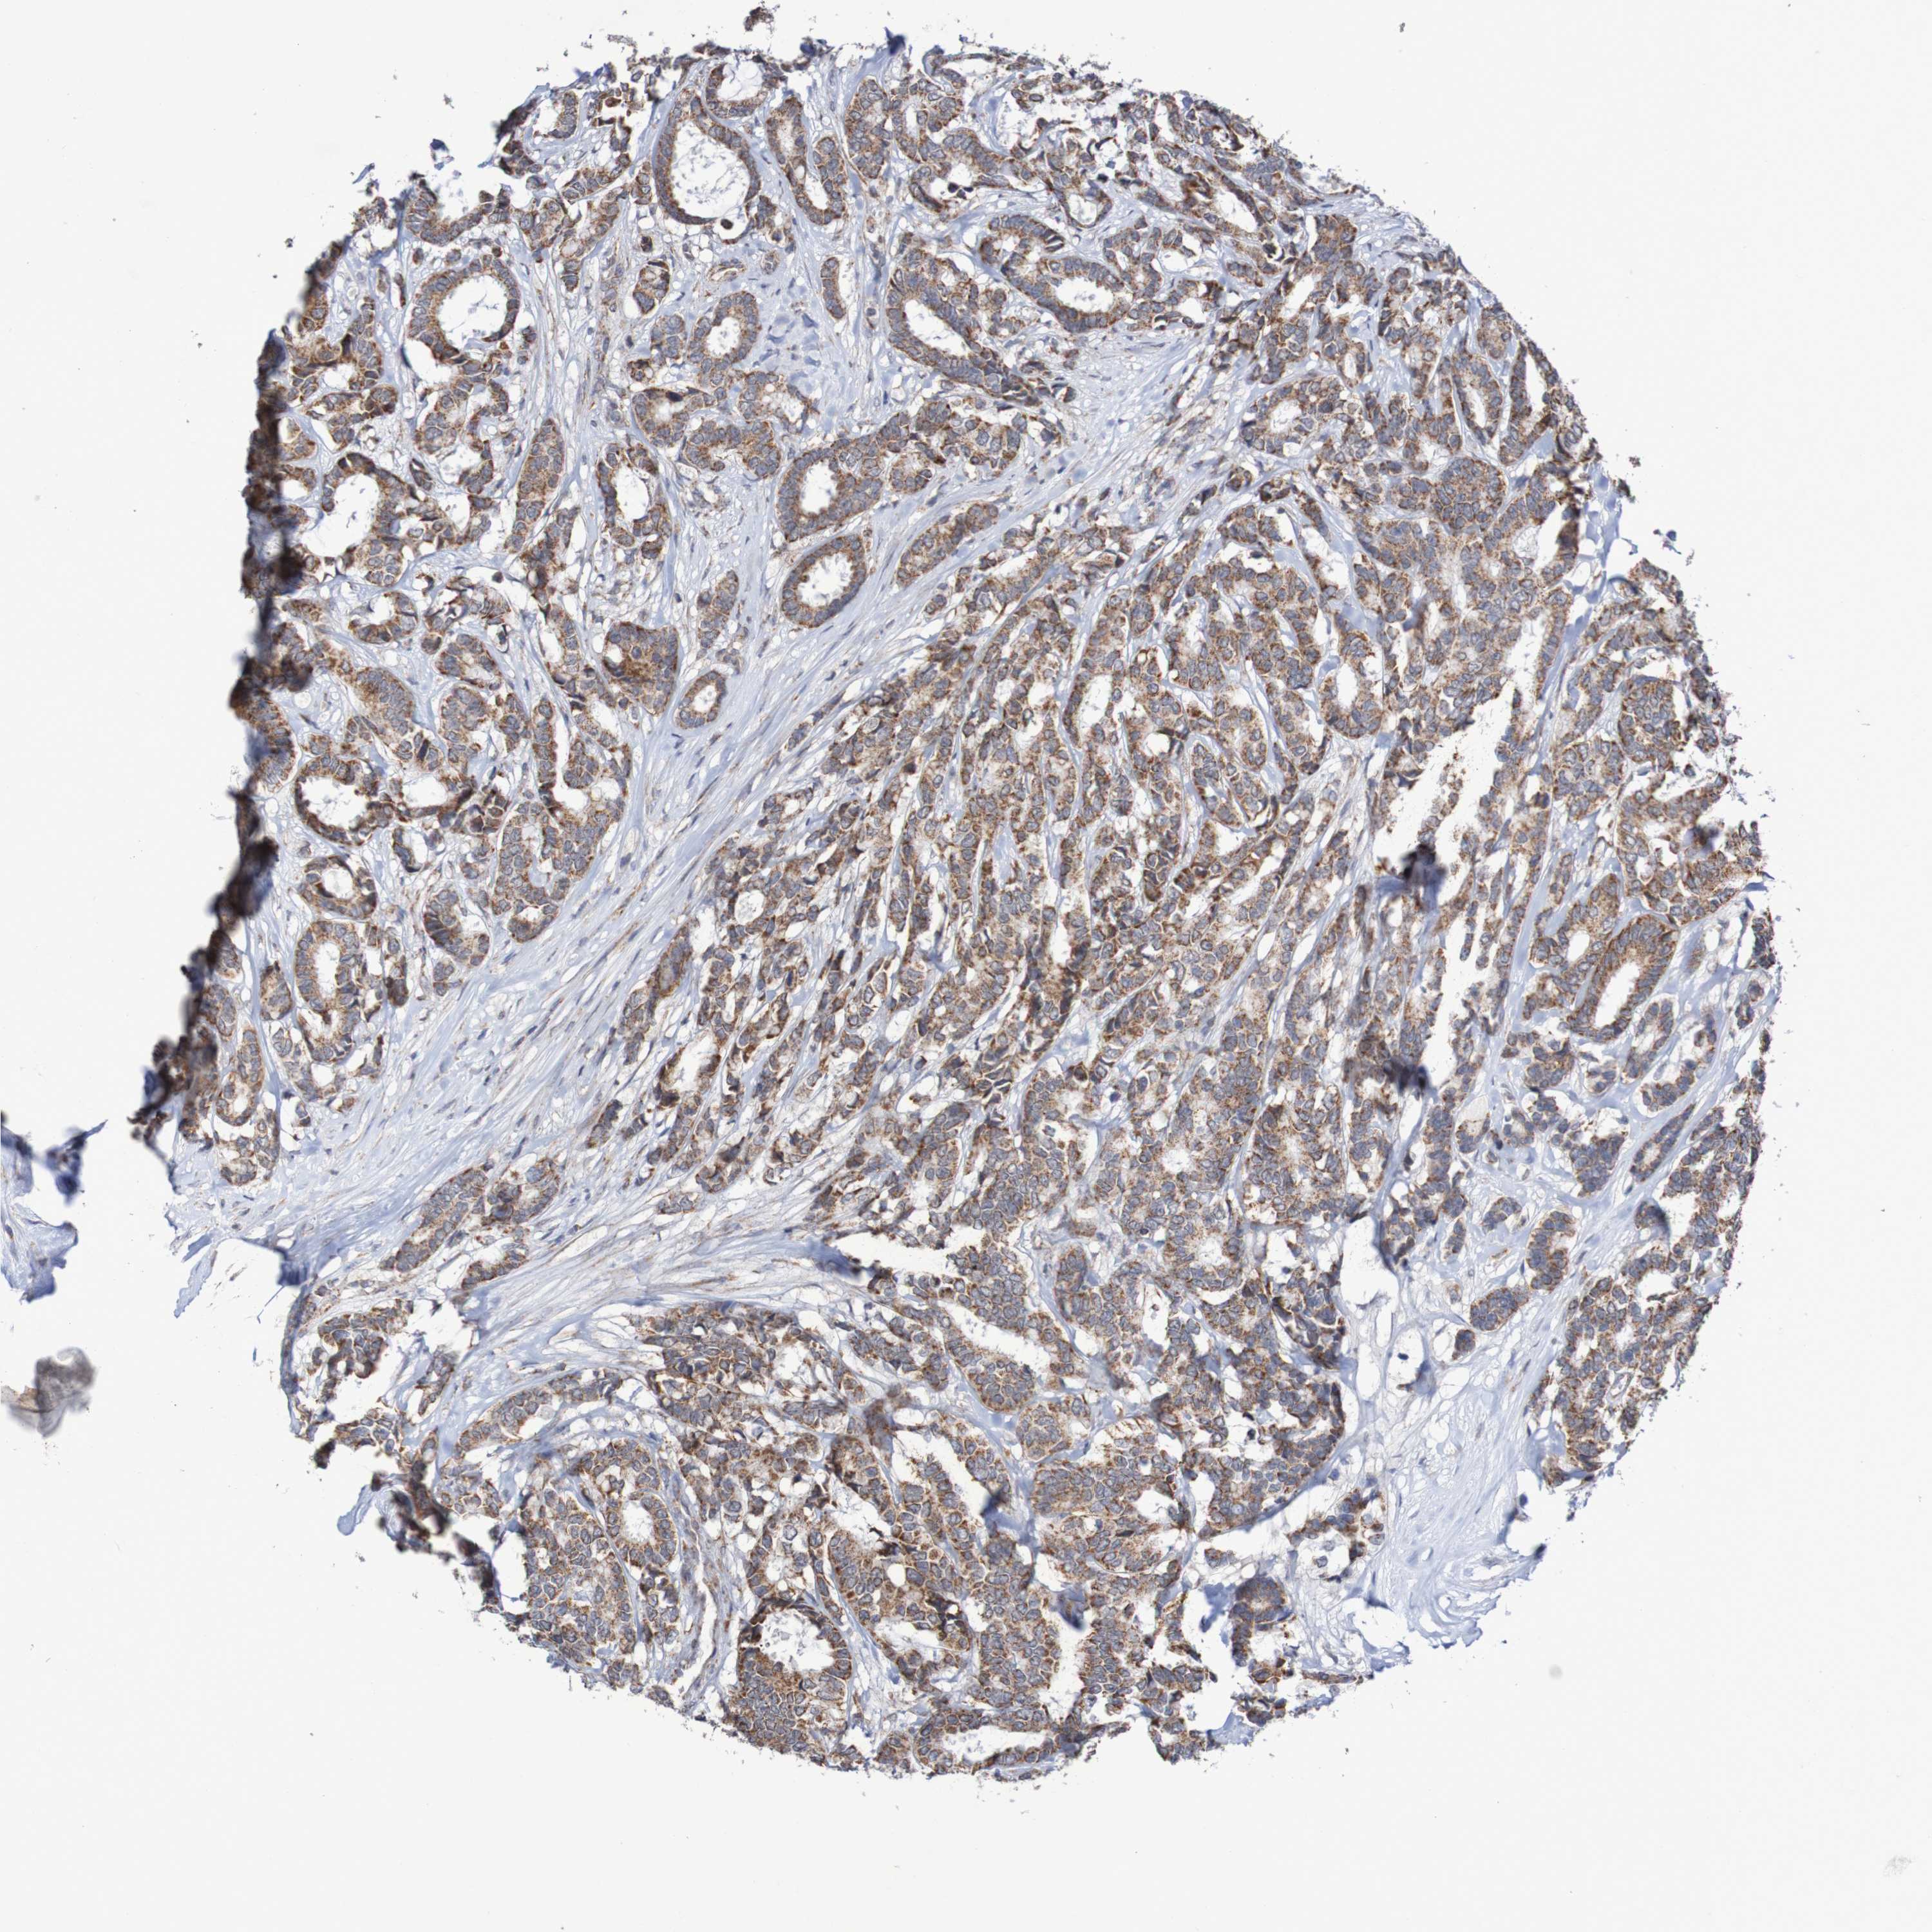

CANCER BREAST CANCER Show tissue menu

BRCA TCGA BRCA VALIDATION PROTEIN EXPRESSION